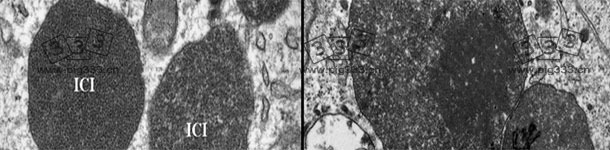

猪圆环病毒2型(PCV2)已经成为对生猪生产破坏性最大的病毒,造成相当大的经济影响(直接损失和控制疾病的花费)。PCV2是断奶仔猪多系统衰竭综合征(PMWS)的病原体,目前被称为PCV2-系统性疾病(PCV2-SD, 图 1)。流行病学和和实验研究已证明基因多样性可能影响PVC2的毒力,表现为在全球范围内出现新的基因型以及重组株的流行。也许这正是为什么PCV2种间分类颇具争议的原因。2008年,欧盟猪圆环病毒病联盟提出了以成对基因序列比较为基础的PCV2基因型标准命名法(www.pcvd.eu)。通过分析PCV2完整和衣壳(ORF2)核苷酸序列确定了2个距离阈值,分别为0.020 和0.035。当2个序列之间的遗传距离大于这两个阈值时,认为这些毒株属于不同的基因型。分析发现了4种基因型,分别命名为PCV2a, PCV2b, PCV2c和 PCV2d(也被称为PCV2b突变型)。